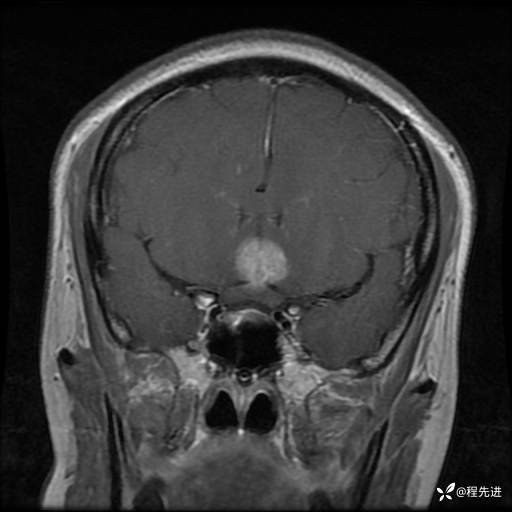

MRI平扫+增强:

T1+C: